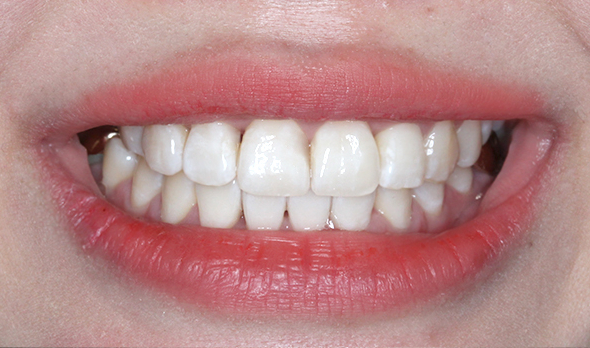

상악 오른쪽 측절치,

사진상으로 왼쪽이

반대로 물리는 반대교합입니다.

간단히 말해 덧니인데

옆에 송곳니와 앞니로 인해

더 도드라져 보이는 상태였습니다.